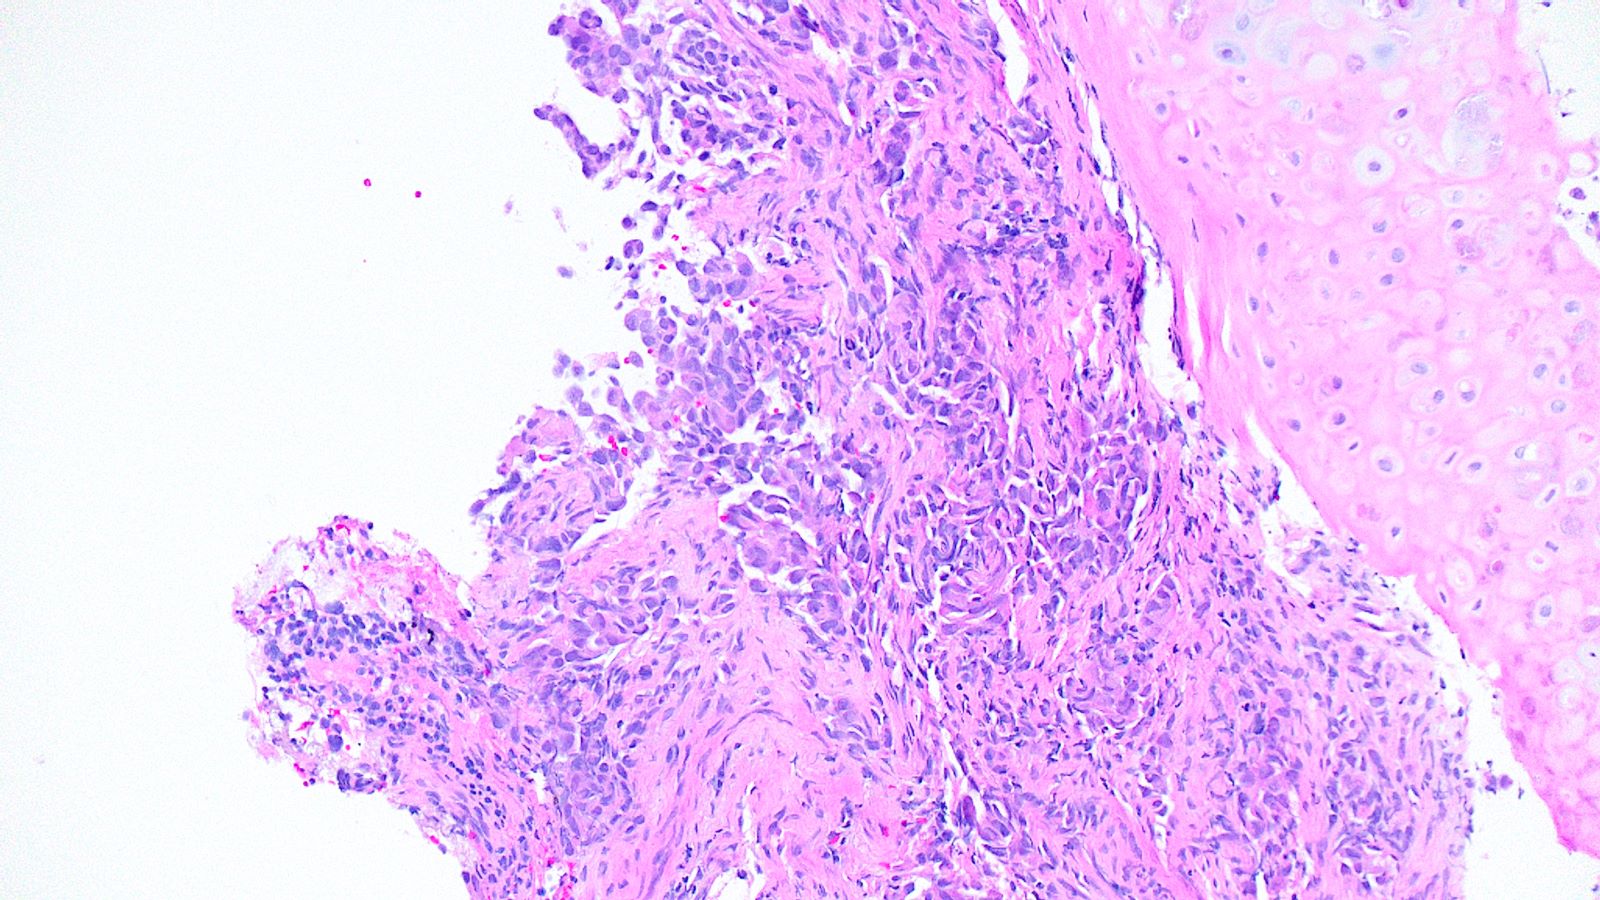

Board review style question #3

A 75 year old man with a 100 pack year smoking history presents with hemoptysis and is found to have a hilar mass and lymphadenopathy. Biopsy of one of the lymph nodes reveals the proliferation seen in the above images. Mitotic activity is approximately 35 mitoses per 2 mm2 and necrosis is present. Immunophenotyping is attempted; however, the block was inadvertently exhausted and stains are not available. What is the best diagnosis that can be rendered?

Board review style answer #3

E. Small cell carcinoma. Small cell carcinoma remains a morphologic diagnosis and does not require immunophenotyping for confirmation. The clinical history and description of the malignant cells are consistent with a diagnosis of small cell carcinoma. Immunophenotyping, including the use of Ki67, is most useful in cases with more ambiguous morphologic features or in crushed biopsies where morphologic features are obscured.